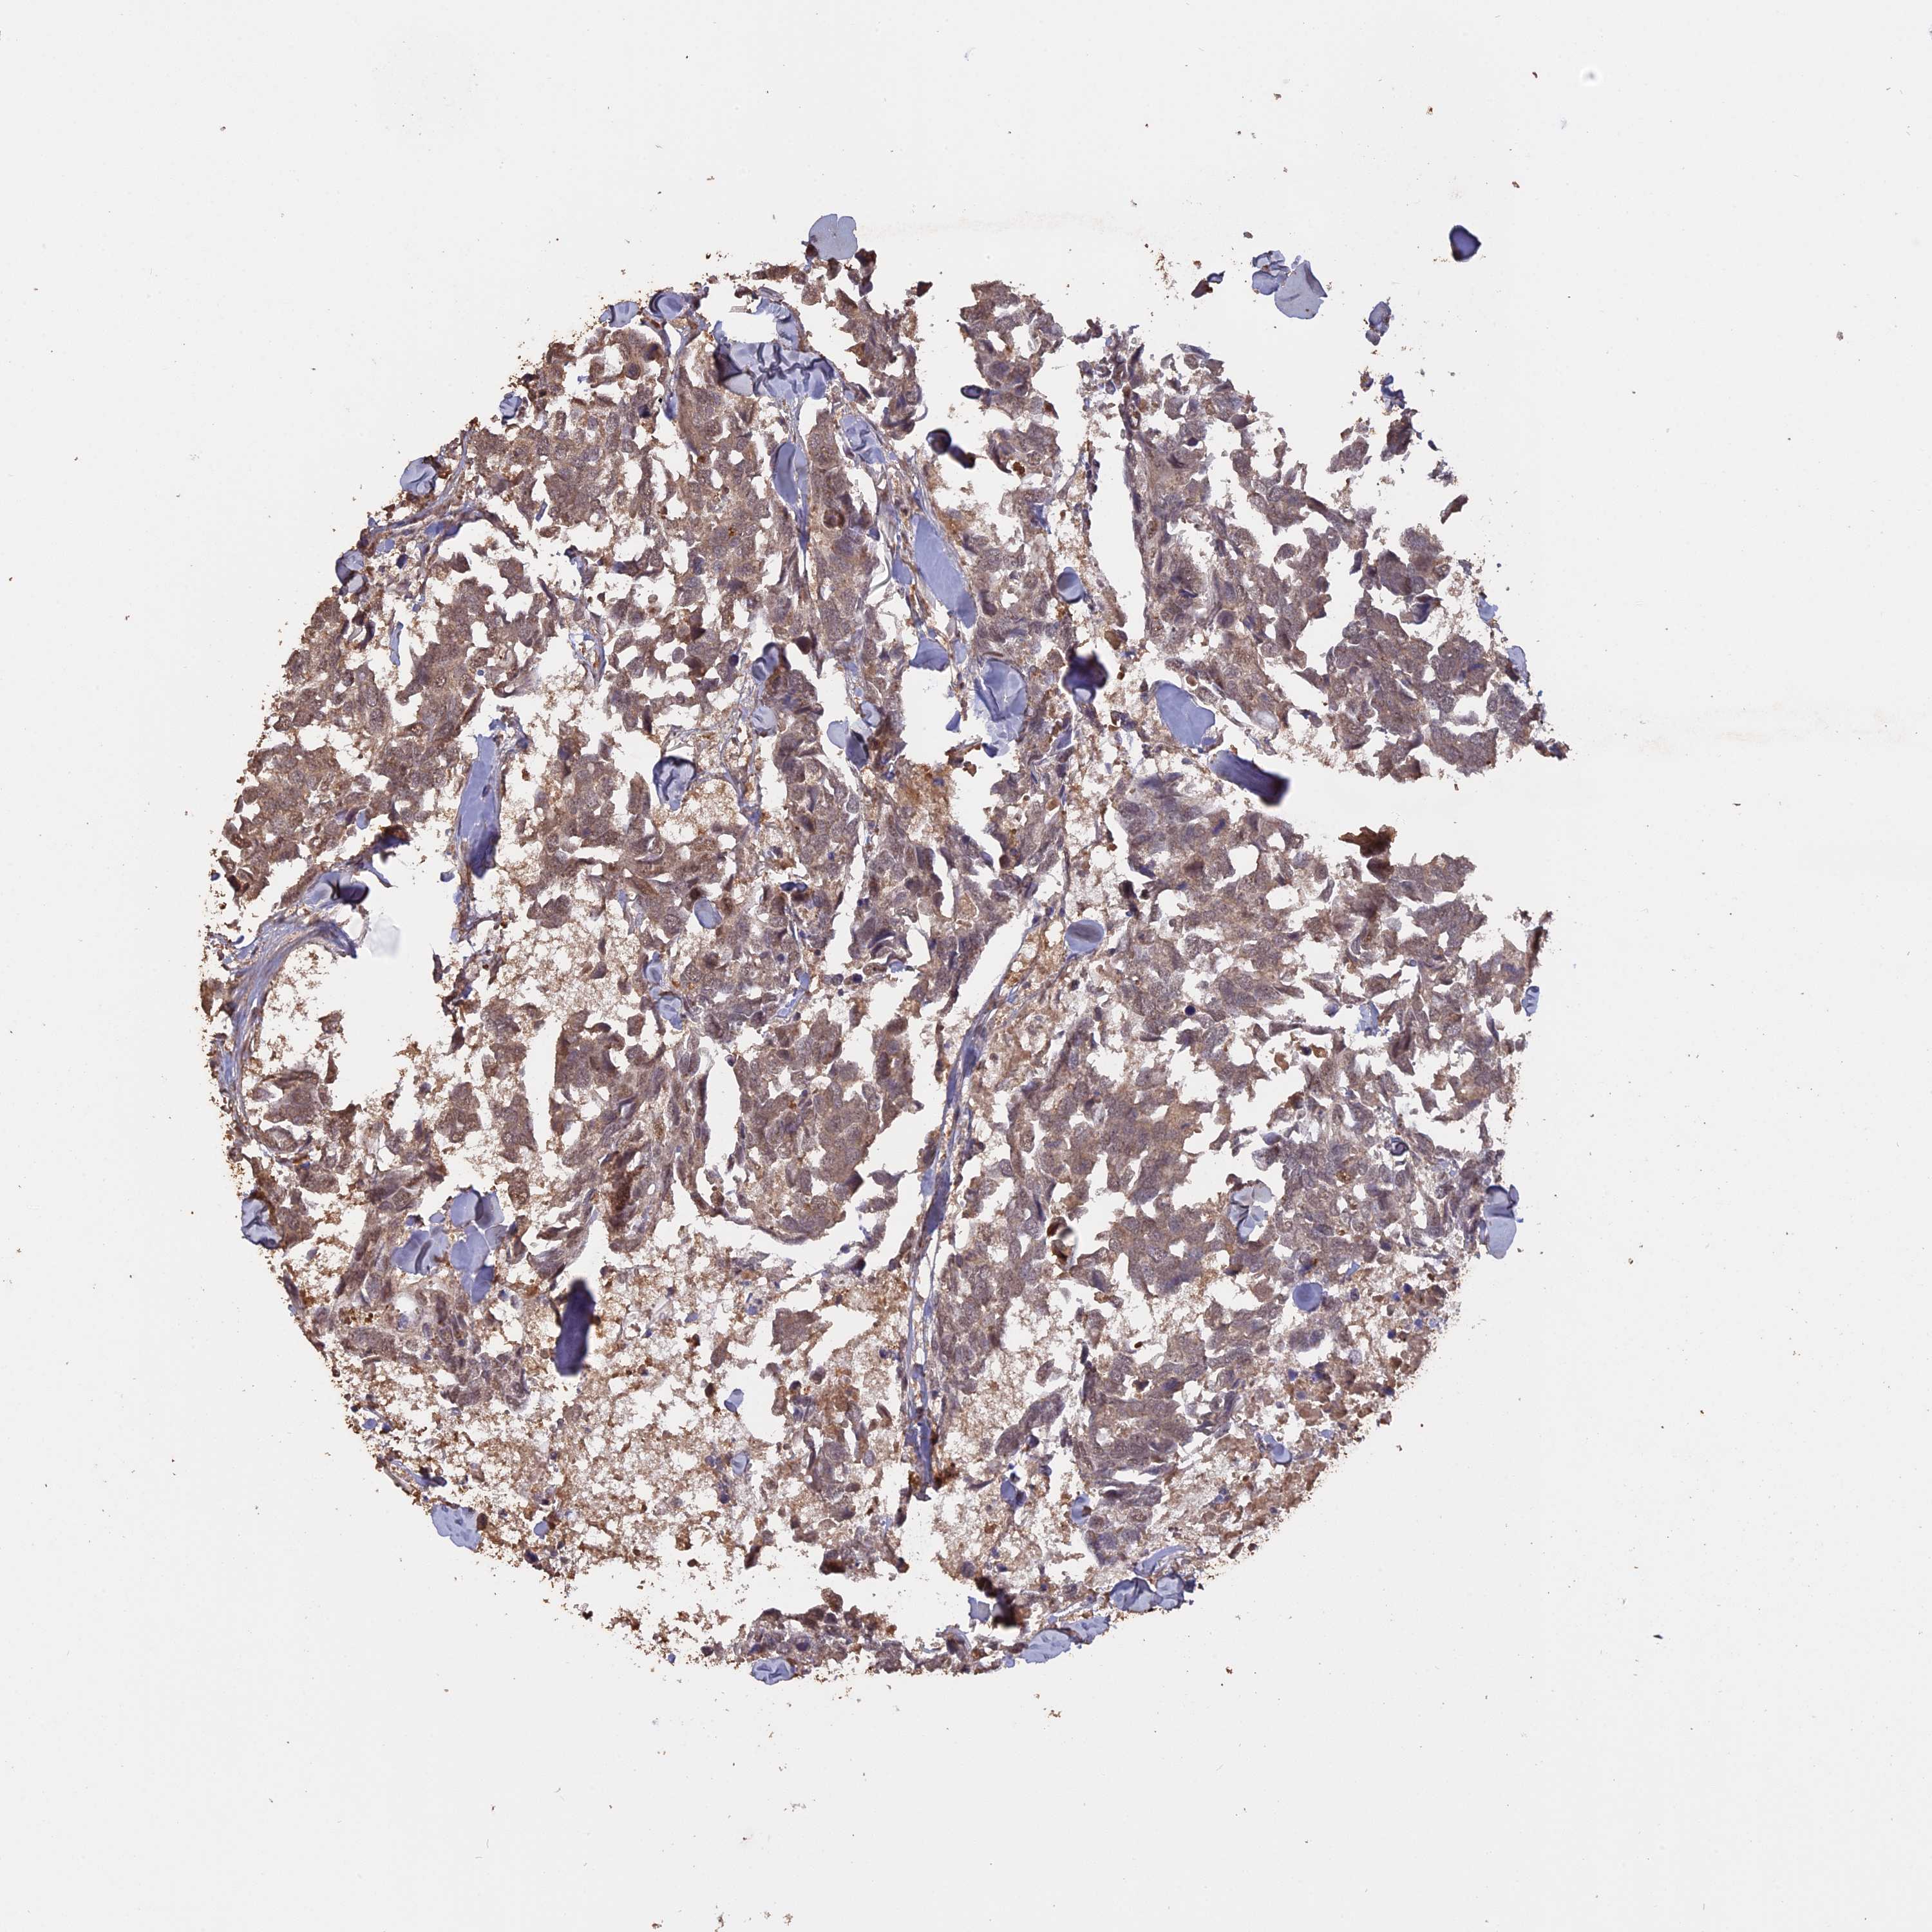

CANCER BREAST CANCER Show tissue menu

BRCA TCGA BRCA VALIDATION PROTEIN EXPRESSION

Breast cancer

Human cancer

Breast invasive carcinoma